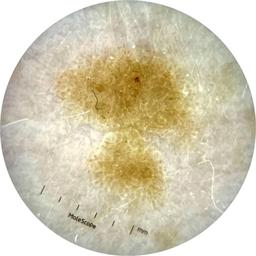

ISIC_9785574

2003 x 2003

Field Value

acquisition_day 148

age_approx 45

anatom_site_1 Head and neck

anatom_site_general head/neck

concomitant_biopsy False

diagnosis_1 Benign

diagnosis_confirm_type single image expert consensus

family_hx_mm True

image_manipulation instrument only

image_type dermoscopic

lesion_id IL_0236417

patient_id IP_8456088

personal_hx_mm True

sex female